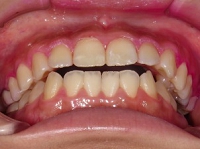

噛み合わせバランス治療(その4)

←治療前/極端なV字型.

当院での咬合治療は,状態や原因に応じて様々なシステムを組み合わせて行っています.このケースでは,前方型のスプリントにて下顎位の精査と誘導を行った後に,固定式の矯正装置(拡大装置とマルチワイヤー装置)で,対応させていただきました.

←治療前/強度な前歯の前突あり

←拡大矯正治療中.

歯列幅を,治療シュミレーションから設定した数値まで,効果的で迅速な矯正装置(緩徐拡大or急速拡大)を選択して左右的に拡大しながら,前歯の状態を整えています.

←ワイヤー矯正中

治療前と比較すると下顎は,強制的に後方に押し込まれた位置から開放されたらしく,自然に前方位を表してきました.

さらに,この下顎位にて上顎の後方歯および下顎にもワイヤー矯正を施しバランス矯正治療は終了となりました(非抜歯矯正)↓.

↑矯正治療中 ↑矯正治療後

動的治療期間28ヶ月29回/費用概算65万円.